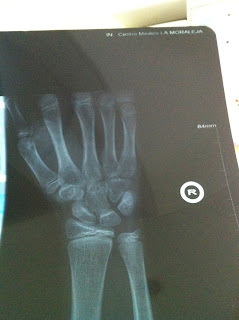

Nästa akuta besök hos doktorn: fick ett samtal från skolan om att Dottern gjort illa en handled på sista rasten - när hon övade att stå på händer - och borde röntga handleden.

Inget brutna ben, men väl en stukning, så hon ska vila handleden i fyra dar.

Daughter sprained her right wrist today at recess, while practicing her handstand. Doctor said four days of rest, nothings broken.